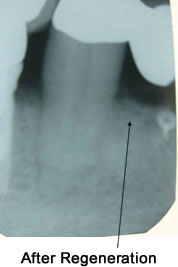

Bone and Tissue Regeneration

When the damage caused by Periodontal Disease is significant, a Bone and Tissue Regeneration procedure may be necessary to save your teeth.

During this treatment, Dr. Zavoral gently folds back the gum and removes the disease-causing bacteria and infection. She will then place membranes, bone grafts and tissue-stimulating proteins to help your body naturally heal and regenerate bone and tissue.

Regeneration of the bone and tissue, along with a strict home care program and increased professional cleanings, will greatly increase your chances of keeping your natural teeth.